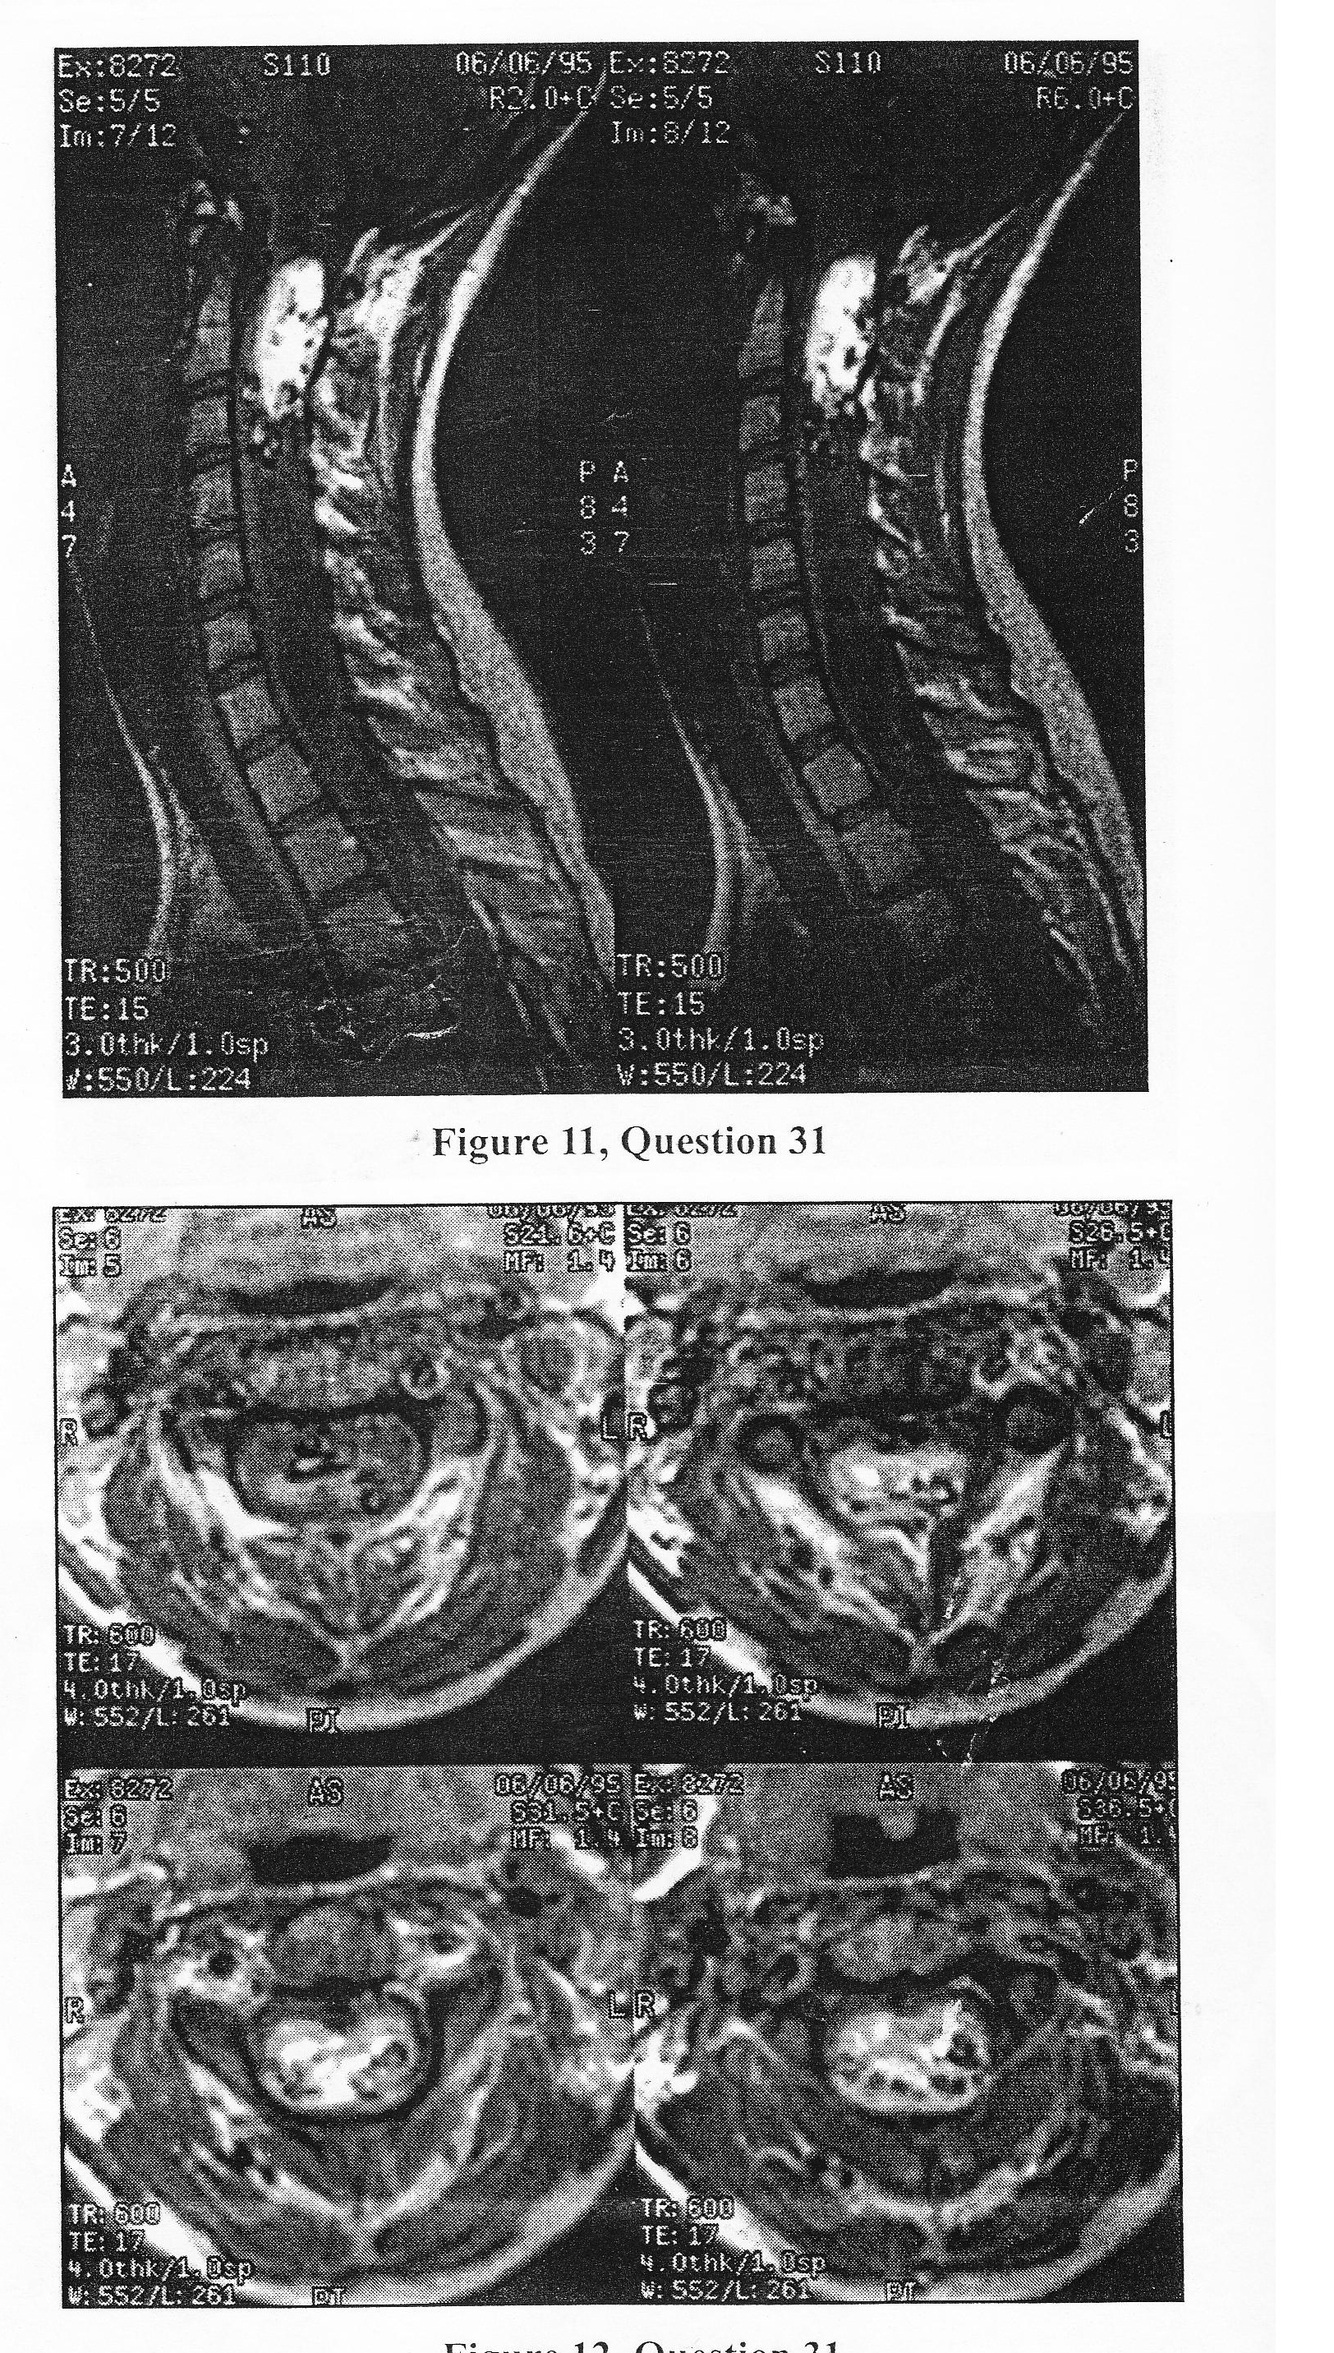

Following a motor-vehicle accident, this 17-year-old female was noted to have a mild central cord syndrome. An MRI of the cervical spine (Figures 11 and 12) revealed a massive tumor which was felt to represent a hemangio-blastoma. Which one of the following statements is MOST IMPORTANT regarding treatment of this lesion?